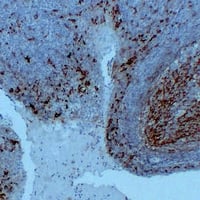

IHC (Immunohistochemistry)

(Immunohistochemical analysis of CD14 staining in human tonsil formalin fixed paraffin embedded tissue section. The section was pre-treated using heat mediated antigen retrieval with sodium citrate buffer (pH 6.0). The section was then incubated with the antibody at room temperature and detected using an HRP conjugated compact polymer system. DAB was used as the chromogen. The section was then counterstained with haematoxylin and mounted with DPX.)